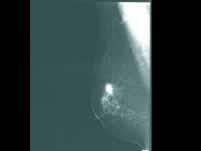

问题 乳腺癌的乳腺X线摄影最为常见的表现是()

选项 A.乳腺内肿块,密度较高,边缘有毛刺 B.乳腺内肿块,密度较高,边缘可见规则晕环 C.乳腺内肿块,密度较高,边缘光滑的是 D.乳腺内肿块,密度较低,边缘光滑 E.乳腺内肿块,密度较低,边缘不光滑

答案 A